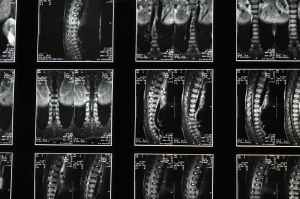

La colonne est aussi sujette à divers problèmes, comme par exemple: prolapsus discal (hernie discale), spondylolisthésis et défaut de l’isthme interarticulaire [24].

La sténose spinale lombaire est un syndrome douloureux et est causé par une insuffisance généralisée du tissu conjonctif. On retrouve aussi les discopathies et les maladies spondylartique dégénérative précoce [95].

La cyphose est très courante chez les SEDh/HSD tout comme la scoliose.

L’ectasie durale a été retrouvé chez les patients SED et Marfan. Bien que souvent les gens n’aient pas de symptômes, il peut notamment y avoir des maux de tête et la position allongée et censée soulager [24].